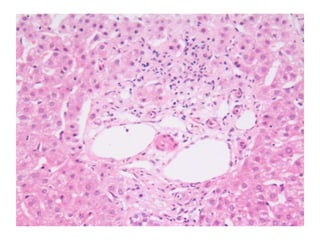

BS09-15303  Clinical history: 56 yo, female. elevated transaminase and anti-mitochondrial antibody.

BS09-15303  Dx: Primary biliary cirrhosis, Scheuer stage 1/4 (Diagnostic biopsy).

BS09-15303 Clinicalhistory: 56 yo, female. elevated transaminase and anti-mitochondrial antibody.

BS09-15303 Dx:Primary biliary cirrhosis, Scheuer stage 1/4 (Diagnostic biopsy).